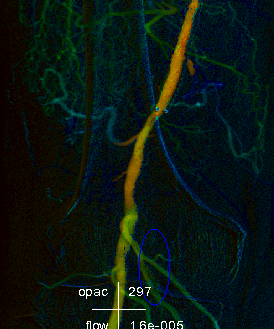

彩色血流编码iFlow基于DSA造影序列一键式生成彩色编码图像,直观且量化的显示血流动力学信息,如造影剂达峰时间等。通过血流达峰时间定量分析对术前术后疗效进行评估。